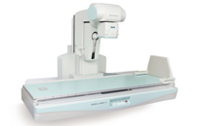

Neo-Vision 是一款数字化透视摄影X射线机,可以完成透视检查、摄影检查及连续摄影检查。岛屿式遥控床体、定制化采集方案、无线动态平板探测器满足多种检查应用。

人性化的设计

精心设计、充分考虑用户需求。

近台控制及遥控控制的床体操作方式,可以应用于各种复杂检查。

操作更加方便,避免病人过度紧张,增加检查的成功率。

高效舒适的操作流程

Neo-Vision产品使用了轻便,可移动的无线动态平板探测器。可以轻松的进行透视及普通X射线摄影的切换。